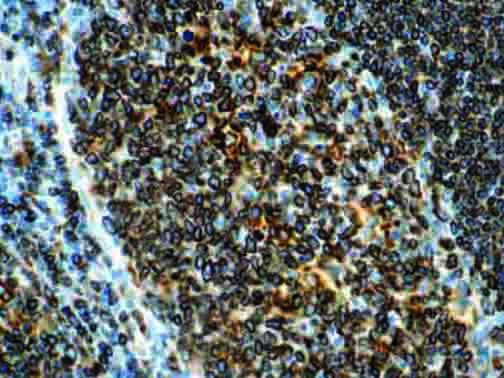

It is the ICU physician who is most likely to witness one of the deadliest manifestations of the abnormal immunological response, the cytokine storm syndrome (CSS). This response is also referred to by some as the cytokine release syndrome (CRS). CSS is characterized by continuous activation and expansion of macrophage and lymphocyte populations, which secrete large amounts of cytokines, causing the cytokine storm. This massive cytokine release is akin to hemophagocytic lymphohistiocytosis (HLH) disease, a syndrome characterized by initial unchecked and persistent activation of cytotoxic T lymphocytes and NK cells.

Clinical and laboratory manifestations of HLH include fever, enlarged liver and/or spleen, neurologic dysfunction, coagulopathy, liver dysfunction, cytopenias (i.e., low levels of erythrocytes, leukocytes, and/or platelets), hypertriglyceridemia, hyperferritinemia, hemophagocytosis, and eventually diminished NK cell activity as the immune system becomes progressively paralyzed. HLH can be familial (primary HLH) or secondary to another disease process (sHLH), such as rheumatic disease, in which it is referred to as macrophage activation syndrome (MAS, characterized by elevated ferritin).